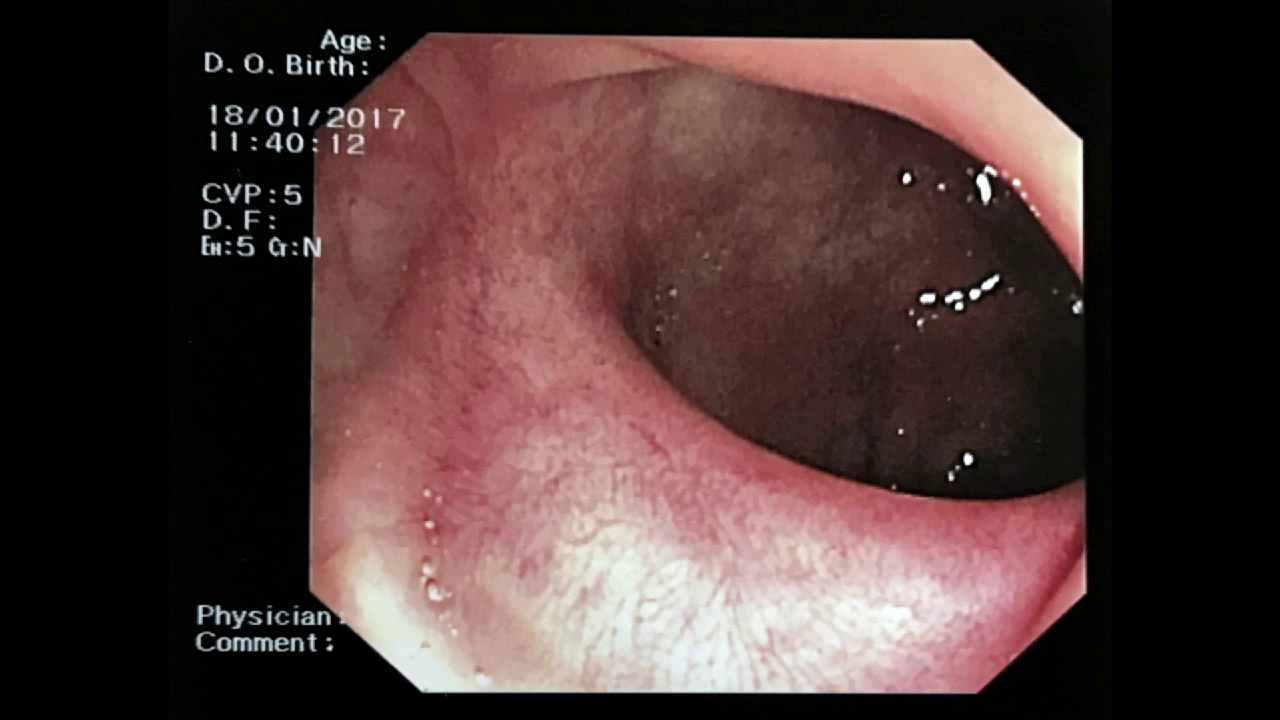

Mujer de 61 años sin antecedentes de interés que presenta rectorragia. En la colonoscopia se aprecia una LST-G de 6 cm de diámetro en el recto que rodea 3/4 partes de su circunferencia y presenta un patrón Kudo IV, NICE 2. El video de la resección se ha editado sólo quitando las partes de intercambio de material, inspección y reevaluación y retirada del material extirpado para poder visualizar lo mejor posible la técnica realizada, inclyendo pequeños errores en la resección y cómo se subsanan. También se ha recortado la coagulación final de los vasos con coagrasper, dejando sólo algunos de los momentos de la revisión final de la escara, aspecto que requiere tiempo. El resultado final anatomopatológico fue de adenoma con componente velloso y DAG. El video se ha editado tras realizar el control a los 6 meses para poder valorar el resultado final. Sobre la zona de la cicatriz se tomaron múltiples biopsias con resultado negativo para adenoma.